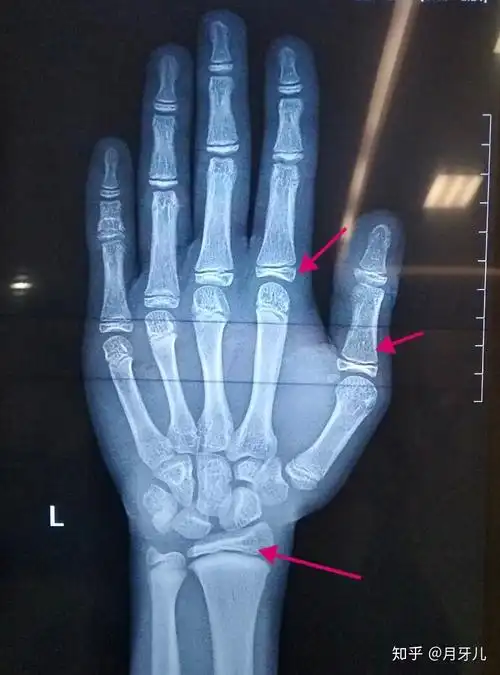

图2图3 刖刑是中国古代墨,劓,刖,宫,杀五刑之一,又称剕刑,指砍去受罚

刖刑又称剕刑,中国古代一种酷刑,指砍去受罚者左脚,右脚或双脚.